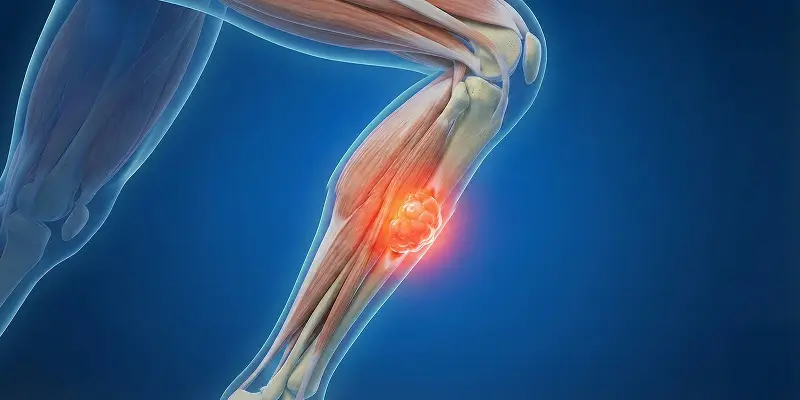

Yumuşak doku sarkomu, kas, yağ, bağ dokusu, sinir ve damar yapılarından köken alan kötü huylu tümörlerdir. Belirtileri, nedenleri, teşhisi ve tedavi yöntemleri.

Sinovyal sarkom, eklem çevresindeki yumuşak dokulardan köken alan kötü huylu yumuşak doku tümörüdür. Belirtileri, teşhis ve tedavi yöntemleri.

Kıkırdak dokusundan kaynaklanan kötü huylu kemik tümörü Kondrosarkom nedir? Kemoterapiye dirençli bu tümörde cerrahinin hayati önemi.